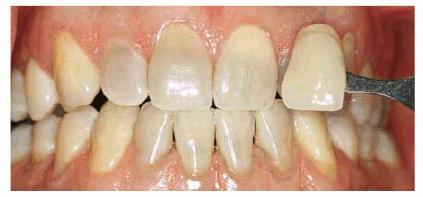

either on an individual tooth or on all teeth (Figures 16-1A, and 16-1B). There are many causes and

Figure 16-1A: An otherwise attractive smile is marred by discolored teeth.

Figure 16-1B: After tooth lightening, the smile is much more pleasing.